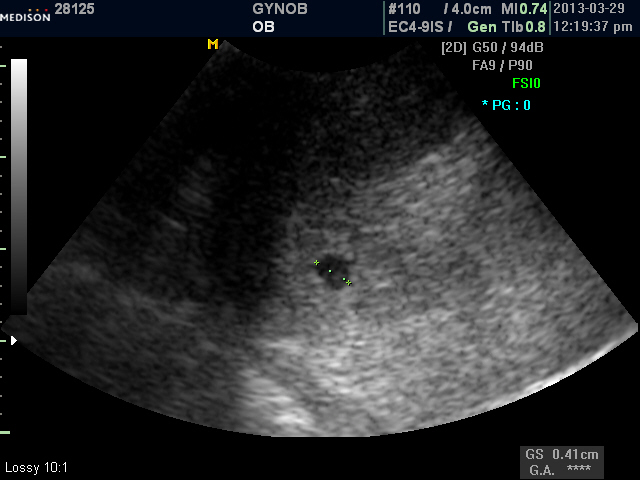

저 역시 기쁘고 왠지 초음파 사진을 보는데 뭉클해지네요 ..

유난히 아기집도 예쁘게 보입니다